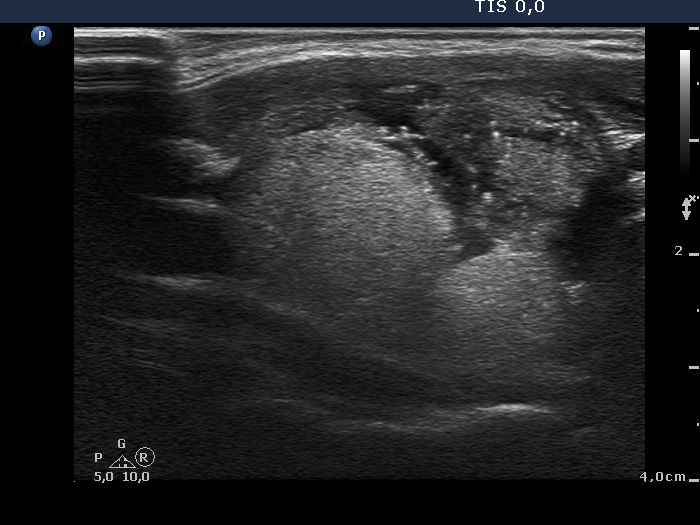

Follicular adenoma - Case 39. |

Clinical presentation: A 44-year-old woman was referred for an evaluation of a nodule discovered by herself. She noticed a lump in her right thyroid 2 years ago. The lesion increased in size in the last 3 months.

Palpation: a hard, not freely moveable nodule in the right lobe.

Ultrasonography revealed a large nodule in the right lobe. The upper two third of the lesion was echonormal, inhomogeneous while the lower third of the mass was hypoechogenic and contained microcalcifications. The presence of a perinodular blood flow was doubtful.